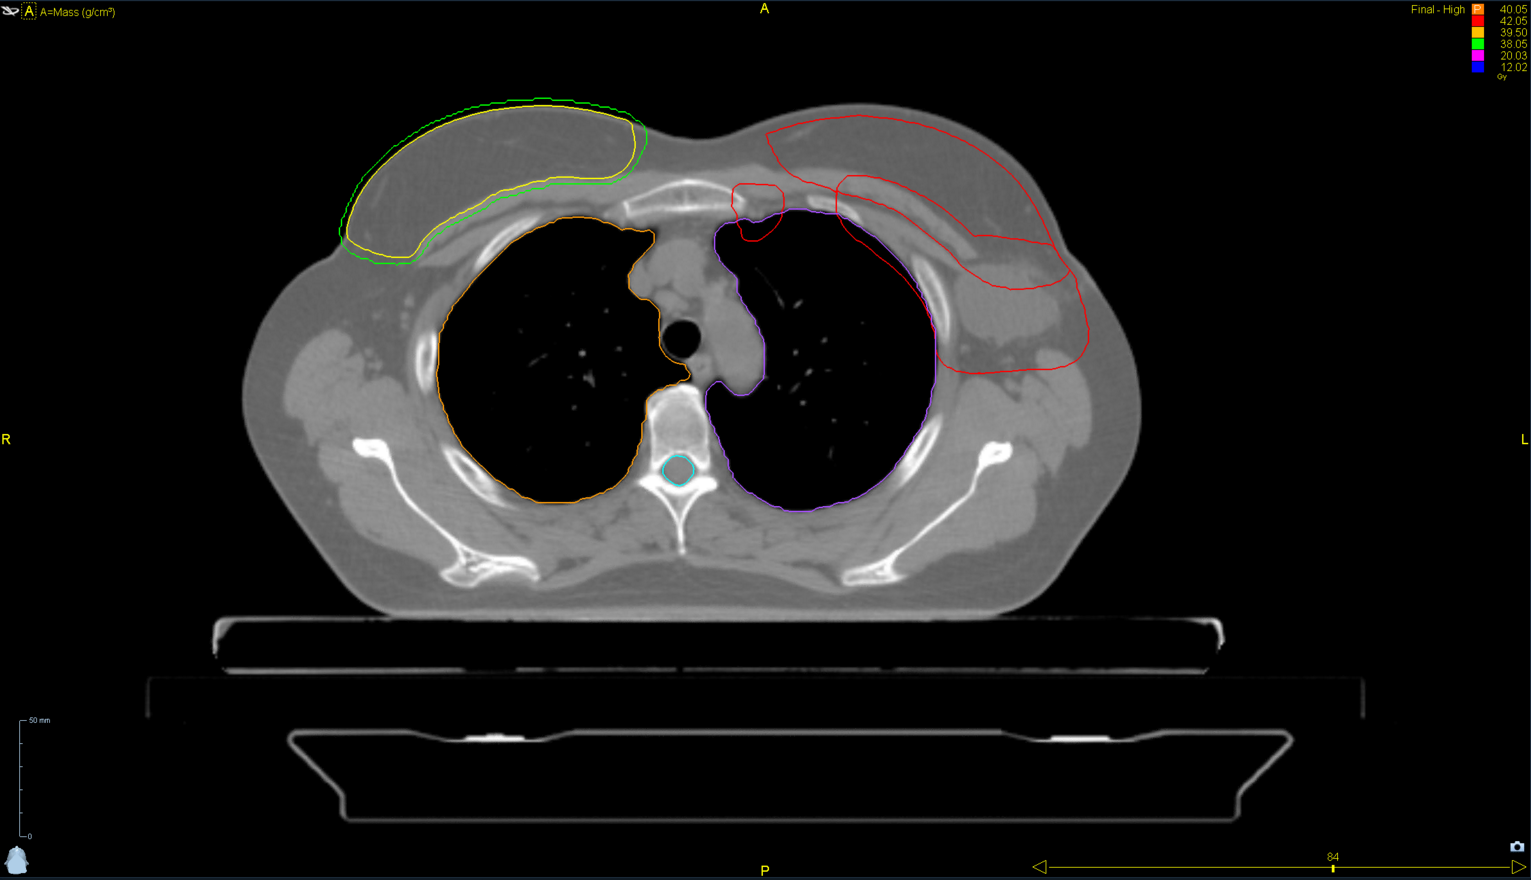

< View All Plan Studies RADIXACT SYSTEM TMI Case History AGE: 76-year-oldGENDER: Male Medical History Immidiate tolerance: Grade II dermatitis with eyelid edema, Grade I conjunctivitis resolved with Sterdex Diagnosis: Squamous cell carcinoma of the right lower eyelid Planning CT Images Treatment Plan Images ClearRT® Images Treatment Planning Highlights Fractionation